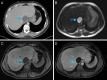

Fig. 1.. Unilocular hepatic hydatid cyst (blue arrow) on CT and MRI.

A: Contrast-enhanced CT: cystic lesion is hypodense with a thickened, enhancing rim; B: T2-weighted MRI: cystic mass is hyperintense with characteristic low-signal intensity rim, probably representing the collagen-rich, outer layer (pericyst) of the hydatid cyst; C. Noncontrast T1-weighted MRI with fat saturation: cystic lesion is hypointense; D: Postcontrast T1-weighted MRI with fat saturation: cystic lesion demonstrates an enhancing rim similar to CT (in panel A), and is without distinct enhancing internal components.